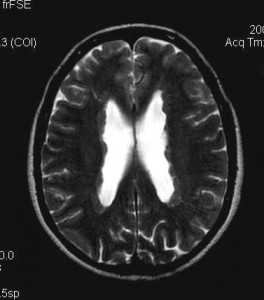

Туберозный склероз. Гамартомы. КТ, Т2-зависимая МРТ и FLAIR

Субэпендимальные, то есть проецирующиеся в желудочек, но растущие со стороны паренхимы мозга, узлы чаще расположены рядом с хвостатым ядром или гипоталамической бороздой сразу за отверстием Монро, реже в области III, IV желудочков и Сильвиева водопровода. На Т2-взвешенных томограммах субэпендимальные узлы умеренно гиперинтенсивны и часто содержат кальцинаты . От астроцитом их отличает не столь яркий сигнал и меньшие размеры. Контрастирование при введении препаратов гадолиния иногда наблюдается и в субэпендимальных узлах , и всегда в астроцитомах.

Туберозный склероз. Субэпендимальные узлы. Аксиальная Т-зависимая МРТ.